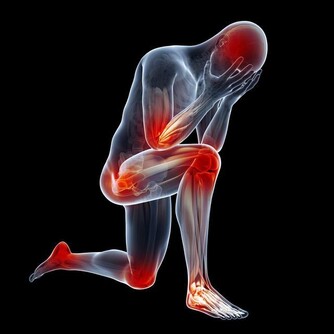

眾所周知,一旦尿酸高了,會引發全身性疾病,首當其衝的就是關節疾病,對於腎臟、血管等都會有不同程度的損害,還會影響血糖引發糖尿病等等。

3、下肢水腫

晚上睡覺的時候身體裡面的尿酸含量是最高的,所以腎小球容易被堵塞,甚至會出現壞死情況,身體裡面的水分沒有辦法很好的排出,容易堆積在身體裡面,這樣就會出現水腫情況,特別是下肢水腫以及眼瞼水腫的情況是比較嚴重的。

4、腰疼

身體裡面的尿酸如果堆積很多,腎臟就會出現非常嚴重的負擔,容易導致腎結石問題出現,腎臟出現問題就會影響到腰部的健康,容易出現疼痛感覺,情況嚴重的話還容易導致失眠症狀出現,所以一定要特別注意。